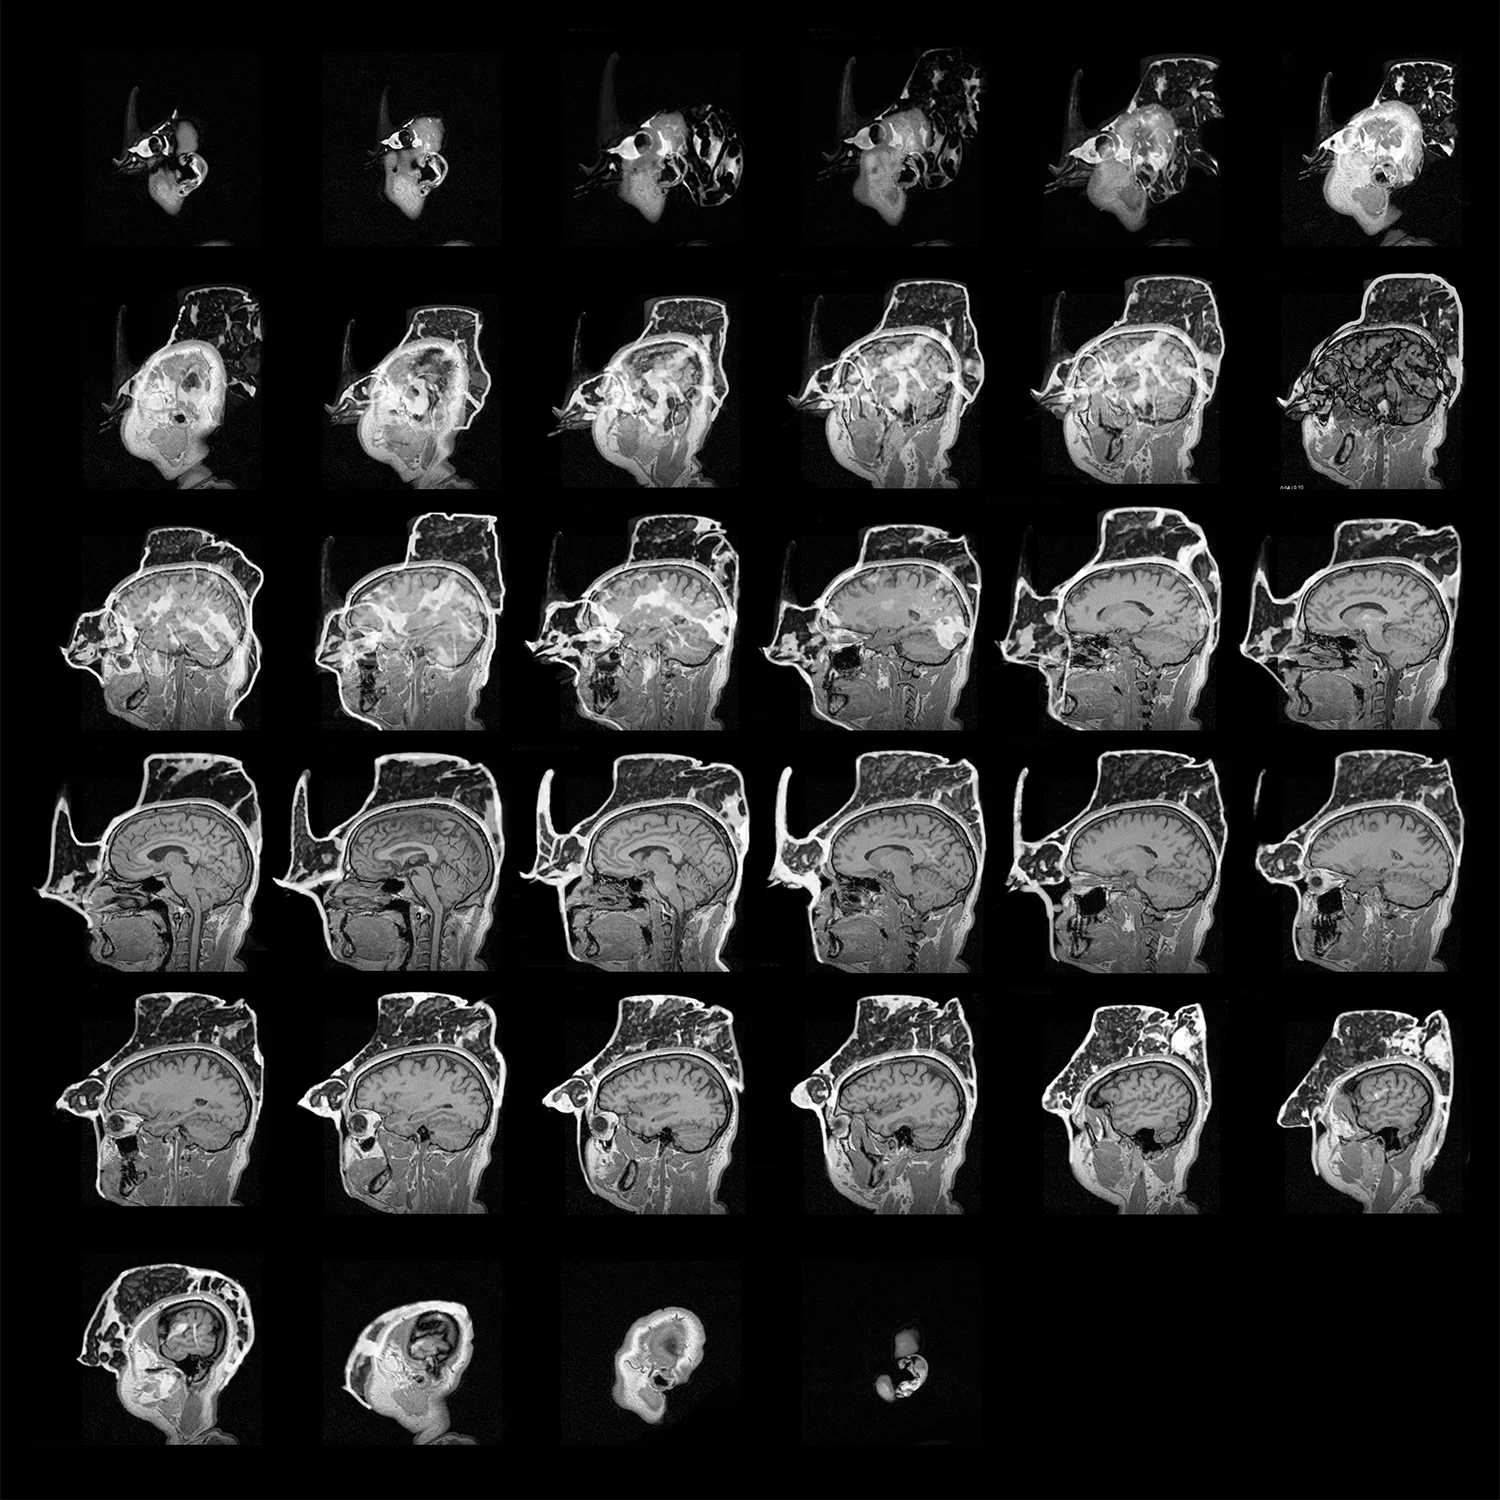

Manipulated MRI Scans of the Human Head

MRI Scans Reconstructed at various resolutions and thresholds